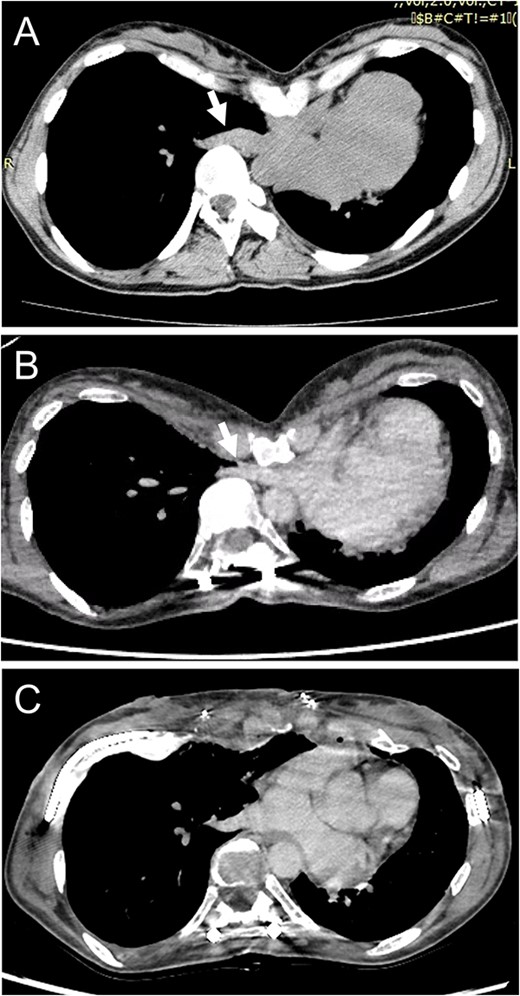

A spirometry test before surgery showed a vital capacity (VC) of 2.0 L (76% of predicted). After surgical repair of her scoliosis, VC was 1.7 L (66% of predicted) and she experienced ventilatory impairment. As part of the imaging test, a chest X-ray demonstrated thoracic scoliosis with a Cobb angle of 62° before surgery, and the curve improved due to a posterior correction of the scoliosis. On the other hand, chest computed tomography (CT) revealed that severe chest excavation presented a lower sternum as an extreme point, and the depressed sternum compressed cardiovascular structures. Notably, a preoperative chest CT indicated that there was no compression of the right inferior pulmonary vein (IPV) (Fig. 1A); however, after scoliosis surgery, severe right IPV stenosis occurred secondary to narrowing of the space between the 9th thoracic vertebrae, which were shifted toward the midline following posterior spinal fusion and lower sternal depression as a result of PE (Fig. 1B). An echocardiogram showed that the systolic right inferior pulmonary venous flow (PVF) increased from 42.5 cm/s to 135 cm/s during changing position.

(A) Chest CT shows no compression of the right inferior pulmonary vein (IPV) before scoliosis repair (arrow). (B) Severe right IPV stenosis is induced by posterior spinal fusion (arrow). (C) Postoperative chest CT indicates that right IPV stenosis is released by elevation of the depressed sternum.

According to these imaging results, exacerbation of dyspnea was attributed to a ventilation-perfusion mismatch because of severe right IPV stenosis. We planned to perform surgery for PE repair to achieve surgical release of the IPV stenosis. The patient underwent a Combined Ravitch and Nuss (CRN) procedure. Thoracoscopy revealed IPV distention due to compression by the severely depressed sternum. The sternal depression was corrected with separation of the 4th–7th costal cartilages, followed by sternal elevation using two pectus bars. She was discharged on the 11th postoperative day without any complications. A postoperative chest CT exhibited an improvement of sternal depression and the right IPV stenosis (Fig. 1C). An echocardiogram revealed that the systolic PVF changed from 49.7 cm/s to 75.7 cm/s during postural changes, and the increase in PVF was mitigated, so that her shortness of breath was relieved postoperatively.